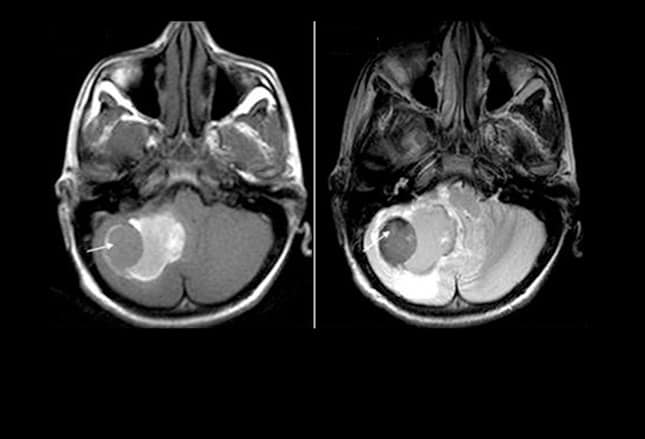

Мр картина венозной ангиомы левой гемисферы мозжечка - 96 фото